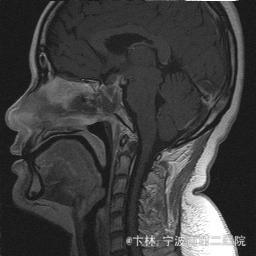

40岁女性,因“双眼视力下降三月余伴停经1个月余”入院。 患者三月前无明显诱因下出现双眼视力下降,视物模糊,尤以左眼为甚,只能近距离看到手动,无头痛、头晕,无恶心、呕吐,无视物旋转,无行走困难等不适,患者曾在某眼科医院就诊治疗,考虑为双眼视神经炎,予以营养,补液对症等治疗(具体不详),情况不见好转,近一月来患者月经停止,来我院神经外科门诊,予以查头颅CT,头颅MRI,提示“垂体大腺瘤”,为求进一步治疗收住入院

予以完善血,尿,粪常规检查,及凝血功能全套,输血功能全套及垂体功能全套,蝶鞍冠状CT等术前检查措施,行经蝶入路垂体瘤切除术。术后予以对症,补液,调节血电解质等治疗,患者视力明显改善,复查头颅MRI提示肿瘤基本全切,一周后患者出院。

此病人颅内垂体瘤体积较大,突破鞍隔压迫视交叉,故患者视力视野障碍为首发症状,该肿瘤主体有大部分向蝶窦腔生长,因此采用经蝶手术入路,肿瘤切除满意,术后患者视力视野恢复满意,。